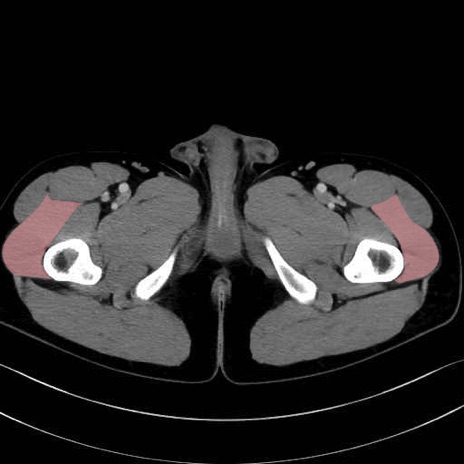

外側広筋(vastus lateralis) のCT画像の解剖

外側広筋 (Vastus lateralis)